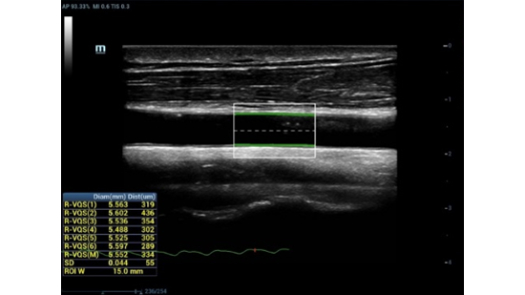

??? ??

? ???? ??? ???? ??

? ??? ???? ?? ???? ?? ??